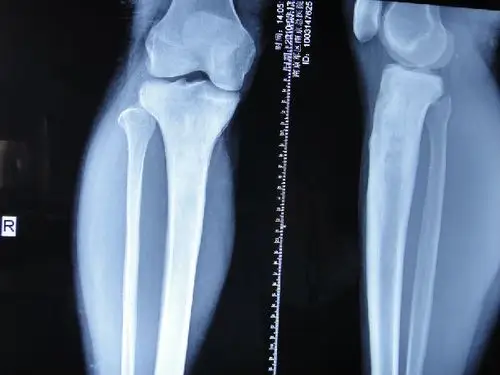

急性化脓性骨髓炎的影像学表现

左胫骨慢性骨髓炎

慢性骨髓炎的症状与诊断科普